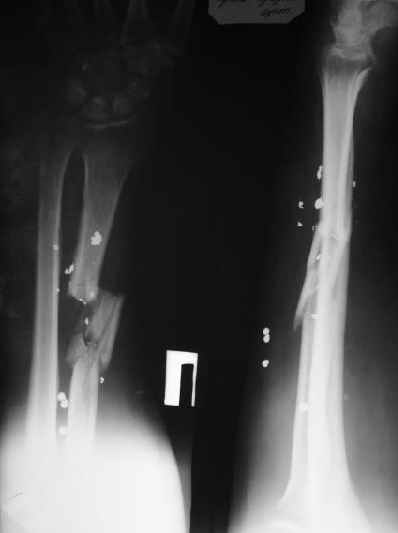

Огнестрельный перелом луча

Мужчина 36 лет 5 мес. назад получил дробовое ранение правого предплечья с переломом лучевой кости, повреждением лучевой артерии и срединного нерва.

В больнице по месту жительства обрабатывали рану, сделали несвободную кожную пластику, синтезировали спицей интрамедуллярно, потом убрали. Свищей нет. Линейный рубец по лучевой стороне, приживший лоскут по ладонной (см. картинку). Cращение не произошло (см. снимок). Нейрохирурги что-то надеются сделать, но условием ставят стабилизацию лучевой кости. Какой вариант тут предпочесть? Представляется оптимальным аппаратом дозированно подправить длину и ось, и закрыто ввести интрамедуллярный стержень. Не особо даже рассчитывая на сращение, а только восстановить форму и длину кости, и создать "эндопротез диафиза". Или подумать про какие-то другие варианты? A male 36 years old 5 month ago sustained a gun-shot wound with the radial fracture and lesion of a.radialis and n.medianus. Debridement was performed at the initial hospital, full-thickness skin grafting and intramedullary fixation of the radius by a small wire, which later was removed. No sinuses and signs of infection to date. A linear scar on the radial side and the healed flap (see image). Healing was not reached (see x-rays). Neurosurgeons hope to do something with the peripheral nerves but only in case of stabilization of the radius. Which treatment modality should be preferred? I would perform gradual alignment with the Ilizarov, and perform secondary closed nailing. Even not to expect to reach union, just to restore length and alignment with the "shaft endoprosthesis". Or it is worth to think about other options?